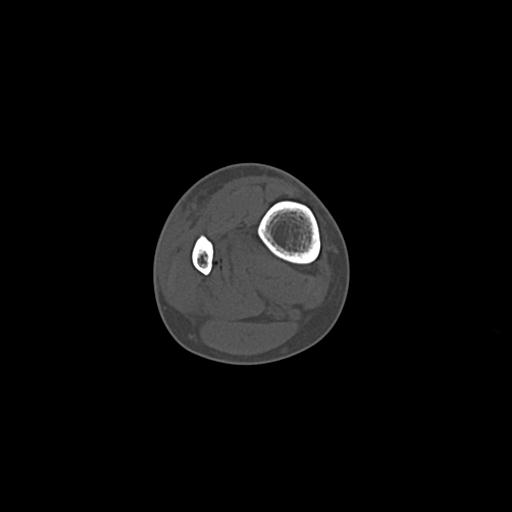

49554 3/13 膝 4R 3/16 4R 1/18 2R 78歳男性 膝蓋骨骨折